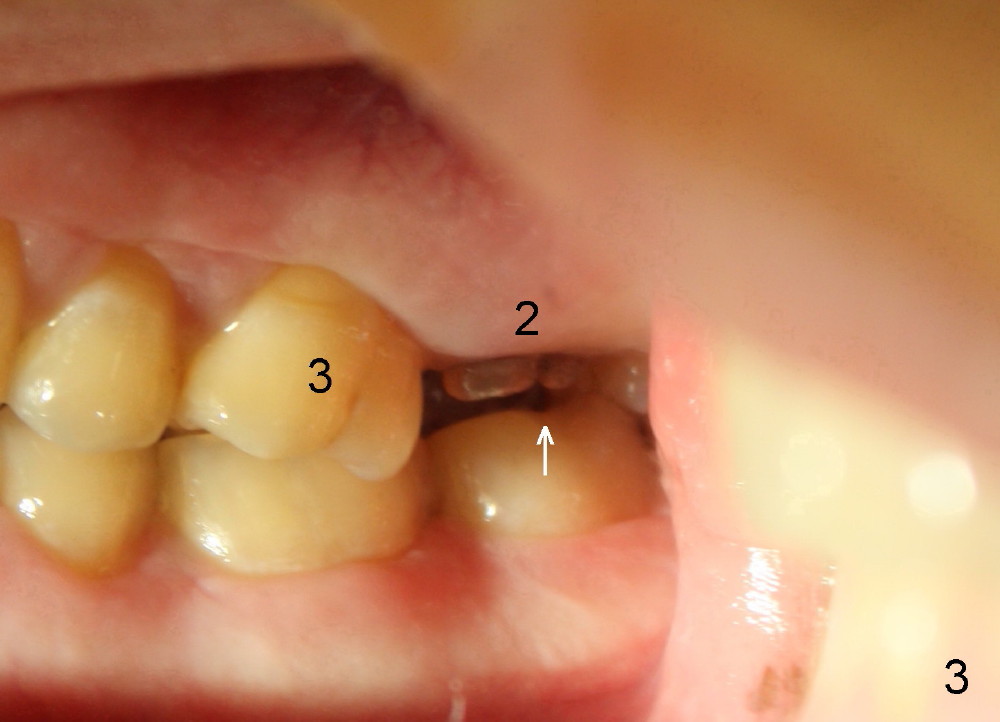

A 42-year-old man is afraid of dentistry. Residual roots of #2 remain untreated for at least 2.5 years (Fig.1). Both the mesiodistal space and the height are limited and unfavorable to restoration (Fig.2,3). Finally he agrees to have treatment, since the tooth #15 is worn so much that it is sensitive to mastication. When the tooth #2 is extracted, the socket is triangular without septum (Fig.4); the bottom of the socket is flat and easy for osteotomy. A 5x17 mm tap has obtained stability once it is placed ~ 14 mm deep (Fig.5). A 5x14 mm implant is placed with insertion torque > 60 Ncm (Fig.6 I), followed by placement of 4x3 mm abutment (A).